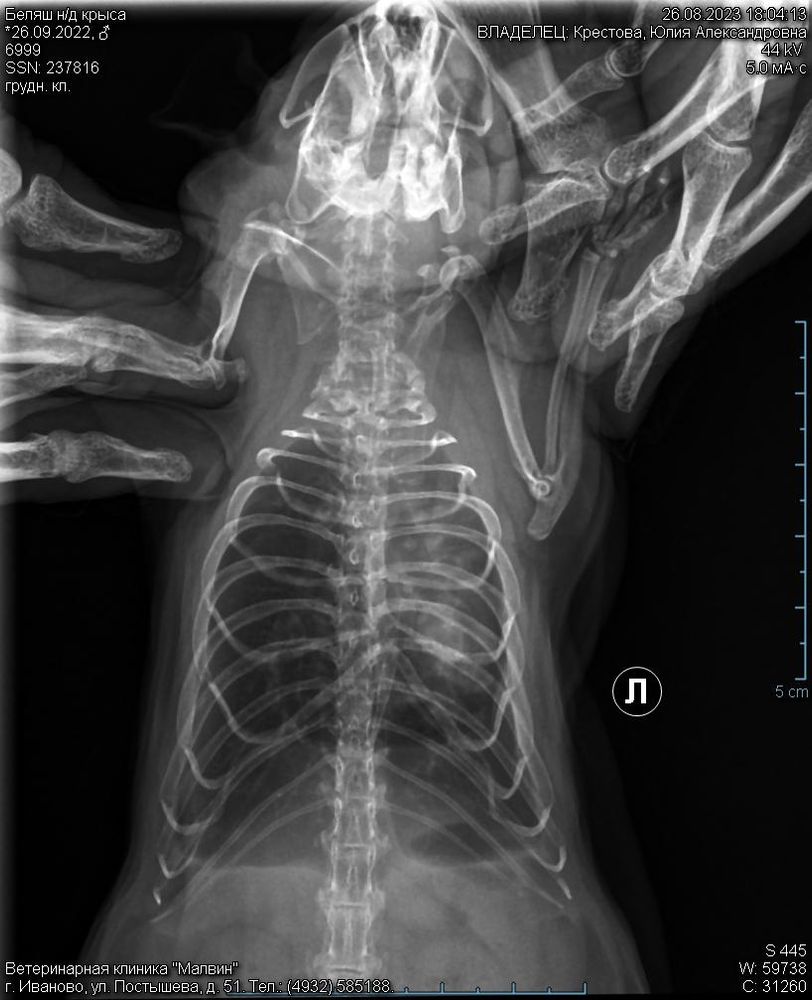

Рентген.